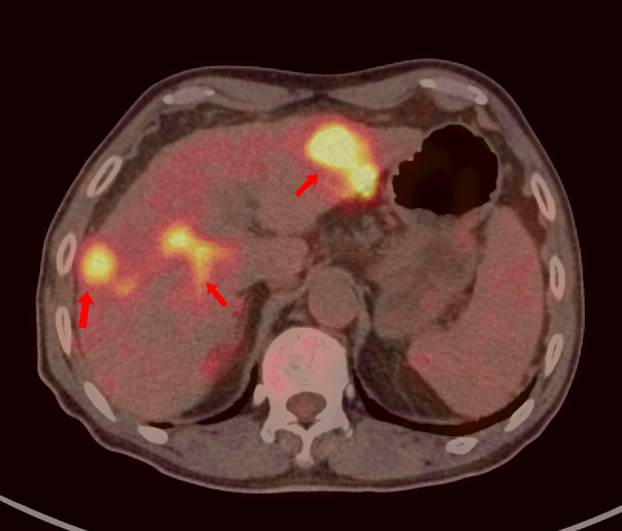

69歲王老伯,發(fā)現(xiàn)肝占位2月余,口服靶向藥物治療,近期外院CT發(fā)現(xiàn)肝多發(fā)占位,診斷為肝細胞肝癌并肝內(nèi)轉(zhuǎn)移,查血腫瘤標記物,AFP 5410ng/ml,有乙肝病史。

PET/CT顯示肝臟左右葉內(nèi)多發(fā)大小不等稍低密度結(jié)節(jié),最大病灶5.8x5.5cm,密度不均,F(xiàn)DG攝取不同程度最高,SUVmax3.9-9.6,門靜脈右支增寬,F(xiàn)DG攝取最高,SUVma 4.9。

PET/CT診斷:原發(fā)性肝細胞肝癌 (多發(fā)結(jié)節(jié)型)并壞死、出血、門靜脈右支癌栓形成;肝硬化